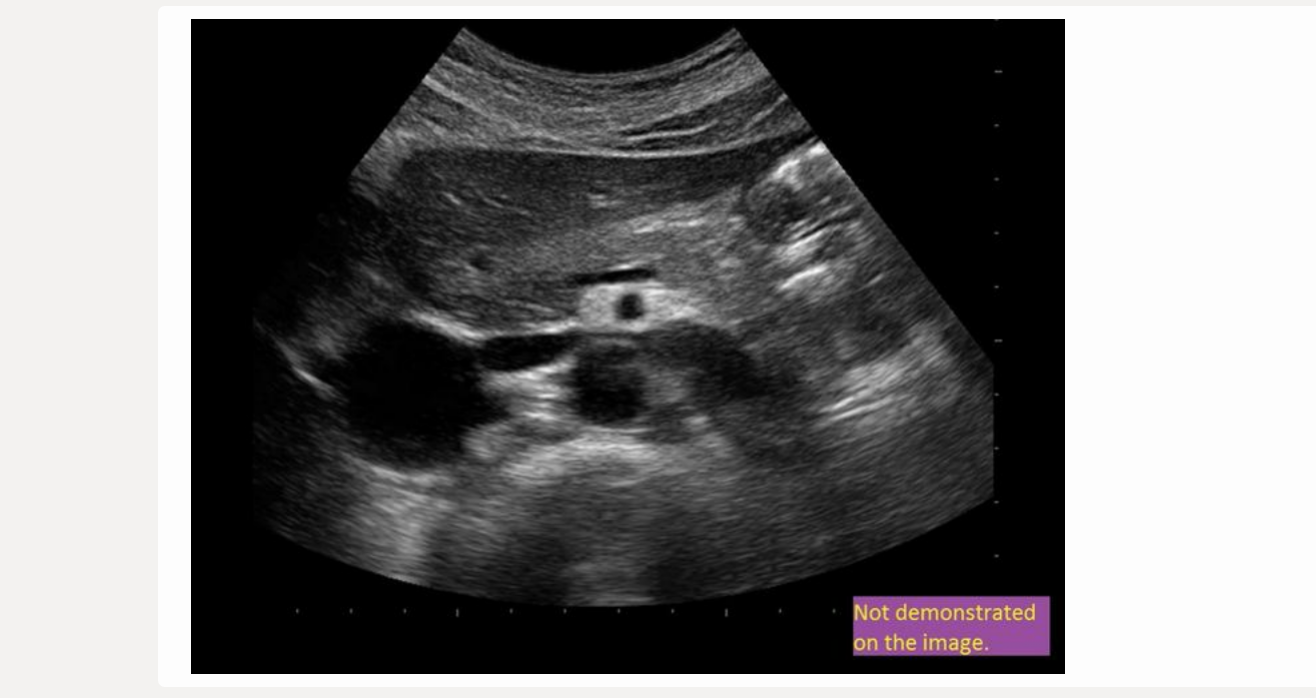

![<p>[IVC = posterior to caudate lobe]</p>](https://knowt-user-attachments.s3.amazonaws.com/37ddafef-a01e-4241-a6eb-4fd43401e918.png)

[IVC = posterior to caudate lobe]

IVC = posterior to caudate lobe